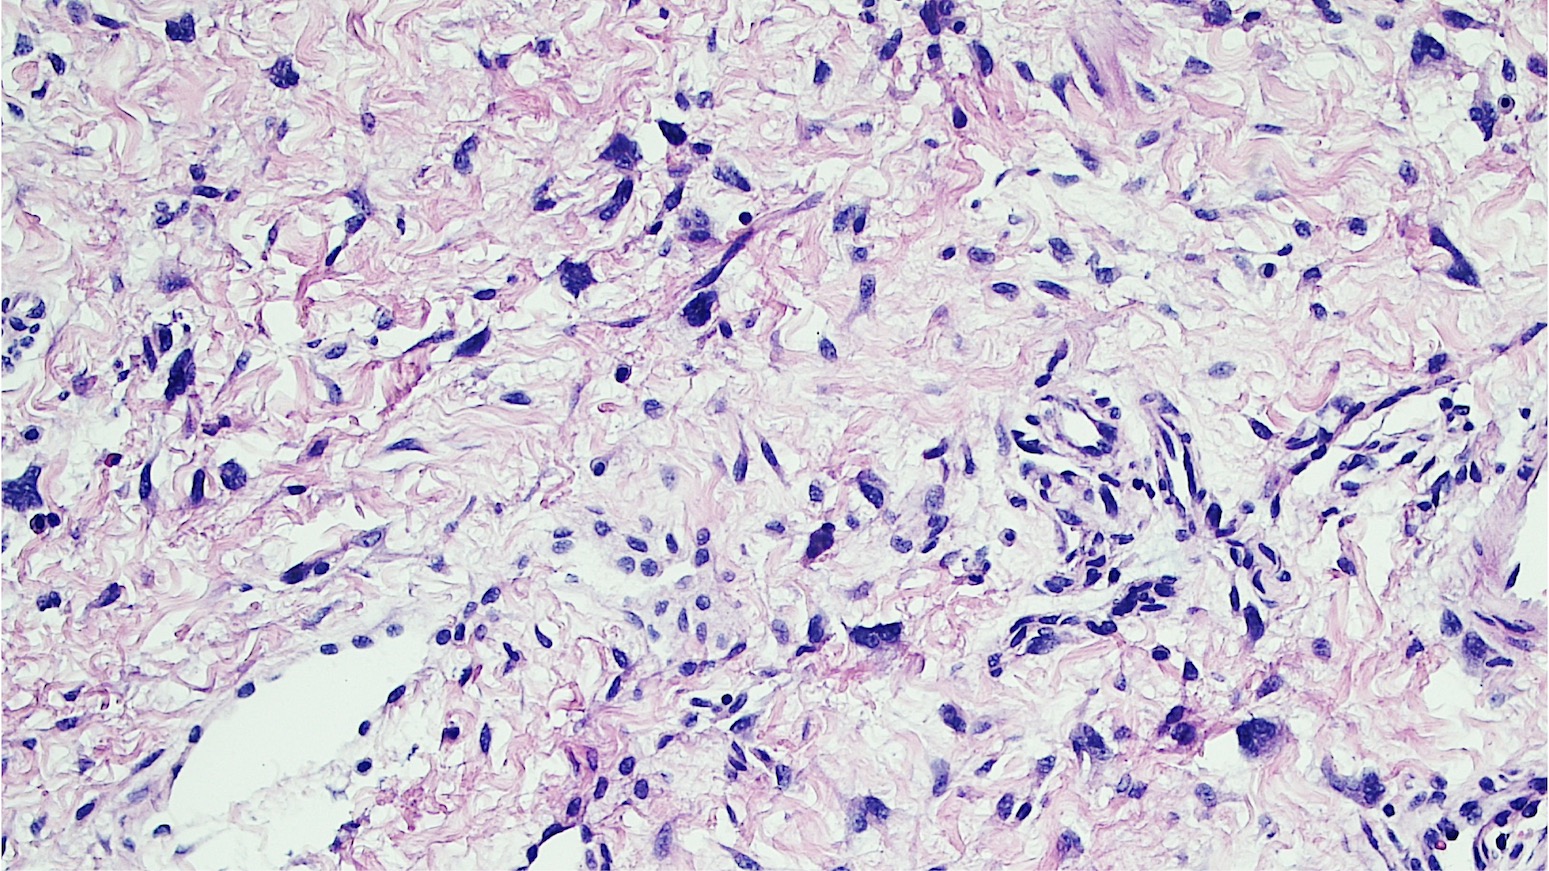

Microscopic (histologic) description

- Polypoid and noncircumscribed, extending to the epithelial / subepithelial interface (J Low Genit Tract Dis 2011;15:69, Am J Surg Pathol 2000;24:231)

- 2 stromal cellularity variants: hypocellular form (spindle cells set within a loose collagenous myxoid-like stroma) or hypercellular variant (exhibits marked nuclear pleomorphism and frequent mitoses, including atypical forms), especially during pregnancy, therefore mimicking leiomyosarcoma or rhabdomyosarcoma (Am J Surg Pathol 2000;24:231)

- Overlying squamous epithelium may display reactive changes but without papillomatous architecture or koilocytosis, which distinguishes it from condyloma acuminatum (caused by human papillomavirus) (Am J Surg Pathol 2005;29:460)

- Stellate cells should not be interpreted as sarcoma (J Low Genit Tract Dis 2011;15:134)

- Commonly found around blood vessels or near the epidermal stromal interface

Microscopic (histologic) images

- A 25 year old woman presented with a vulvar mass, measuring 3.0 cm in diameter. The lesion was excised and the H&E image is shown. Which of the following is the most likely diagnosis?